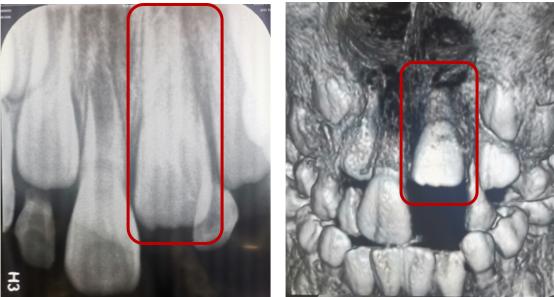

冠根折:累及牙釉质--牙本质--牙骨质折断,累及牙釉质--牙本质--牙骨质--牙髓折断

治疗方案:方案(1)正畸或外科牵引4mm+冠延长+根管治疗+桩核冠修复或根面覆盖;方案(2)拔除患牙后种植修复;方案(3)意向性再植;方案(4)自体牙移植。